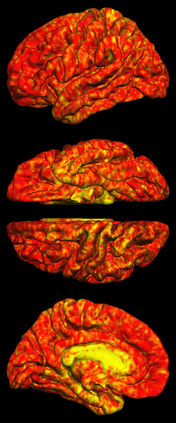

Due to various physical degradation factors and limited counts received, PET image quality needs further improvements. The denoising diffusion probabilistic models (DDPM) are distribution learning-based models, which try to transform a normal distribution into a specific data distribution based on iterative refinements. In this work, we proposed and evaluated different DDPM-based methods for PET image denoising. Under the DDPM framework, one way to perform PET image denoising is to provide the PET image and/or the prior image as the network input. Another way is to supply the prior image as the input with the PET image included in the refinement steps, which can fit for scenarios of different noise levels. 120 18F-FDG datasets and 140 18F-MK-6240 datasets were utilized to evaluate the proposed DDPM-based methods. Quantification show that the DDPM-based frameworks with PET information included can generate better results than the nonlocal mean and Unet-based denoising methods. Adding additional MR prior in the model can help achieve better performance and further reduce the uncertainty during image denoising. Solely relying on MR prior while ignoring the PET information can result in large bias. Regional and surface quantification shows that employing MR prior as the network input while embedding PET image as a data-consistency constraint during inference can achieve the best performance. In summary, DDPM-based PET image denoising is a flexible framework, which can efficiently utilize prior information and achieve better performance than the nonlocal mean and Unet-based denoising methods.